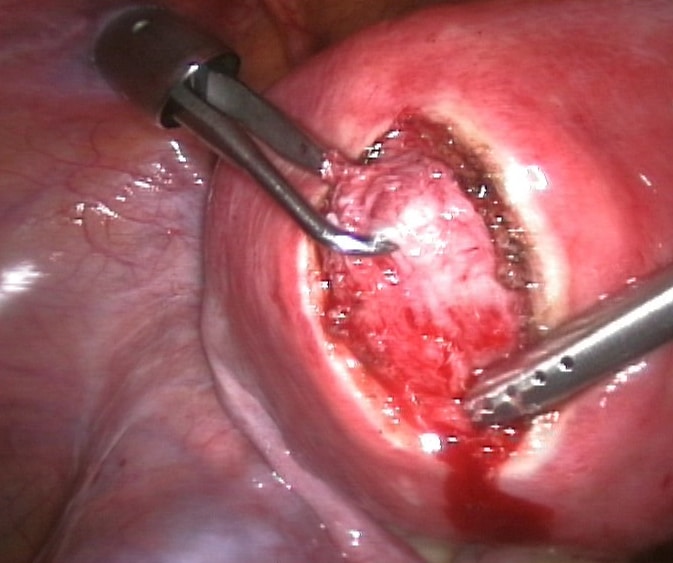

Fig 3

A laparoscopic myomectomy.